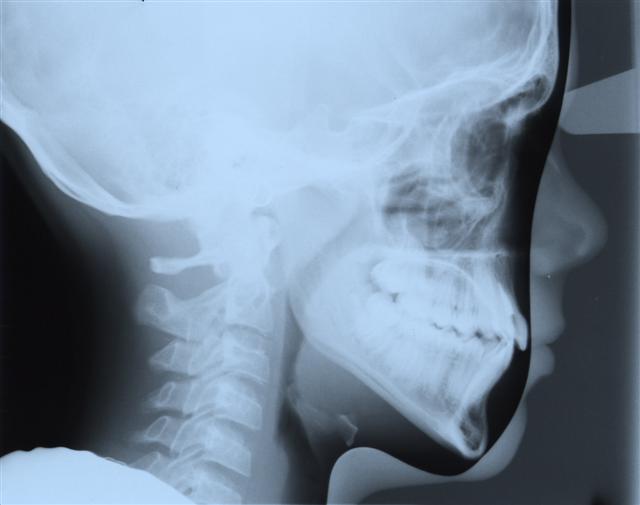

Cephalometric X-Rays

An x-ray of the head that shows whether your teeth are aligned properly and if they are growing properly.